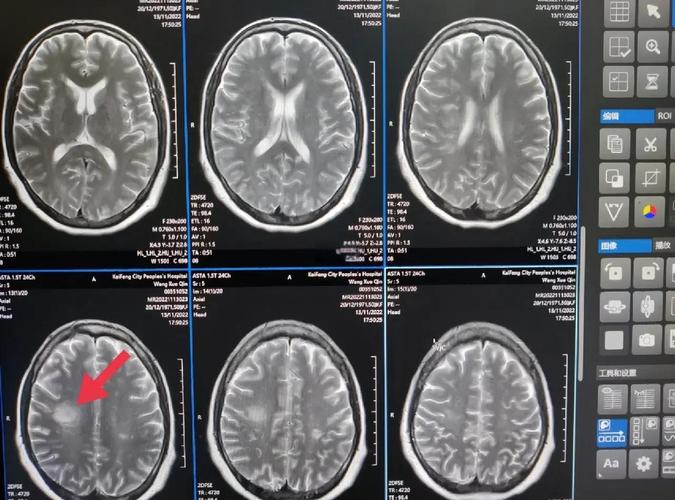

常规的CT检查在发病6小时内,对早期脑梗死的检出率很低(可能低于20%),而特定的磁共振检查(特别是DWI序列)在发病数分钟到数小时内,就能非常敏感地发现脑梗死的早期迹象,检出率可高达90%以上。

- 早期表现: 在发病6小时内,绝大多数脑梗死在CT上完全正常,或者只有一些非常细微、不易察觉的间接征象(如脑沟变浅、脑回模糊),这些征象需要经验丰富的放射科医生才能识别,且特异性不高。

- 何时能看清: 通常在发病6-12小时后,缺血区域的脑细胞开始坏死,水分增多,密度才会明显降低,呈现出低密度灶,24小时后,CT显示会非常清晰。

- 表现: 在DWI图像上,这种“水分子扩散受限”的区域会显示为明显的高信号(亮白色),这个改变在脑缺血发生后的几分钟内就可能开始出现,并且在发病后30分钟到1小时内,诊断的敏感性和特异性就非常高了。